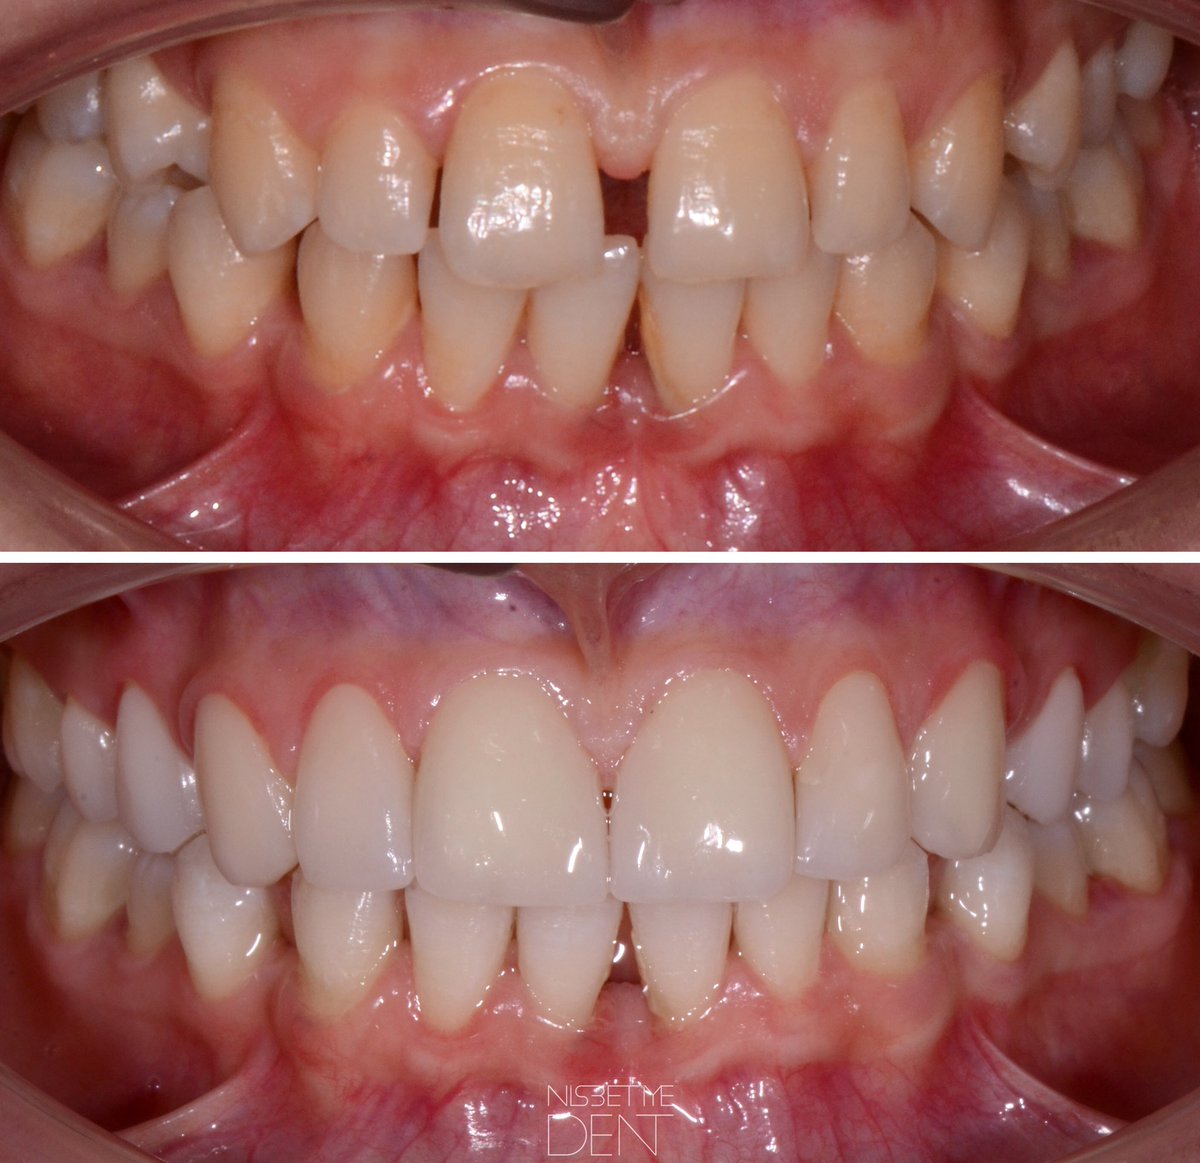

‘Dişler ayrık olunca kısmet de açık olurmuş’ 🤪🤪🤪lafına hiç inanamıyoruz . @ nisbetiyedent #laminates #emax #hollywoodsmile #estheticdentistry 💕✨💕